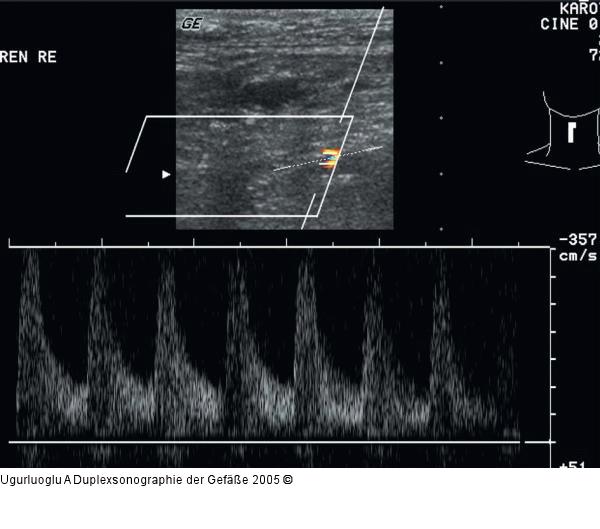

Abbildung 9: Duplexsonographie - Nierenarterienstenose Frequenzspektrum der hochgradigen Abgangsstenose der rechten Nierenarterie, Vsyst: 340 cm/sec., Vdiast: 105 cm/sec. |

Frequenzspektrum der hochgradigen Abgangsstenose der rechten Nierenarterie, Vsyst: 340 cm/sec., Vdiast: 105 cm/sec. |